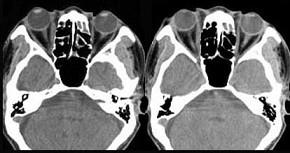

问题 男,36岁,双眼球突出5月余,CT如图所示,应诊断为 ( )

选项 A、眶内脑膜瘤 B、眶内淋巴瘤 C、肌炎型炎性假瘤 D、未见异常 E、眼型Graves病

答案 E